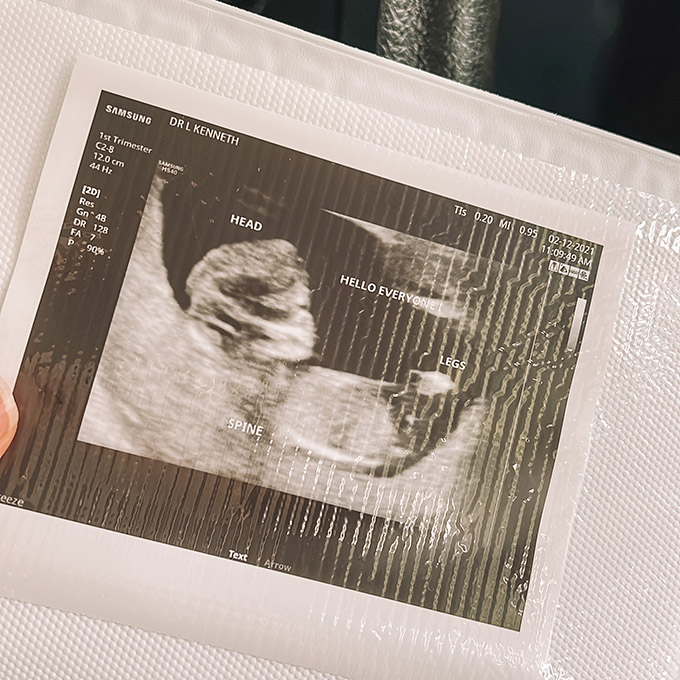

Between weeks 11-13, you will schedule an ultrasound for a nuchal translucency screening. This ultrasound is done on your belly and the technician will be taking some measurements to physically check for chromosomal abnormalities such as Down Syndrome.